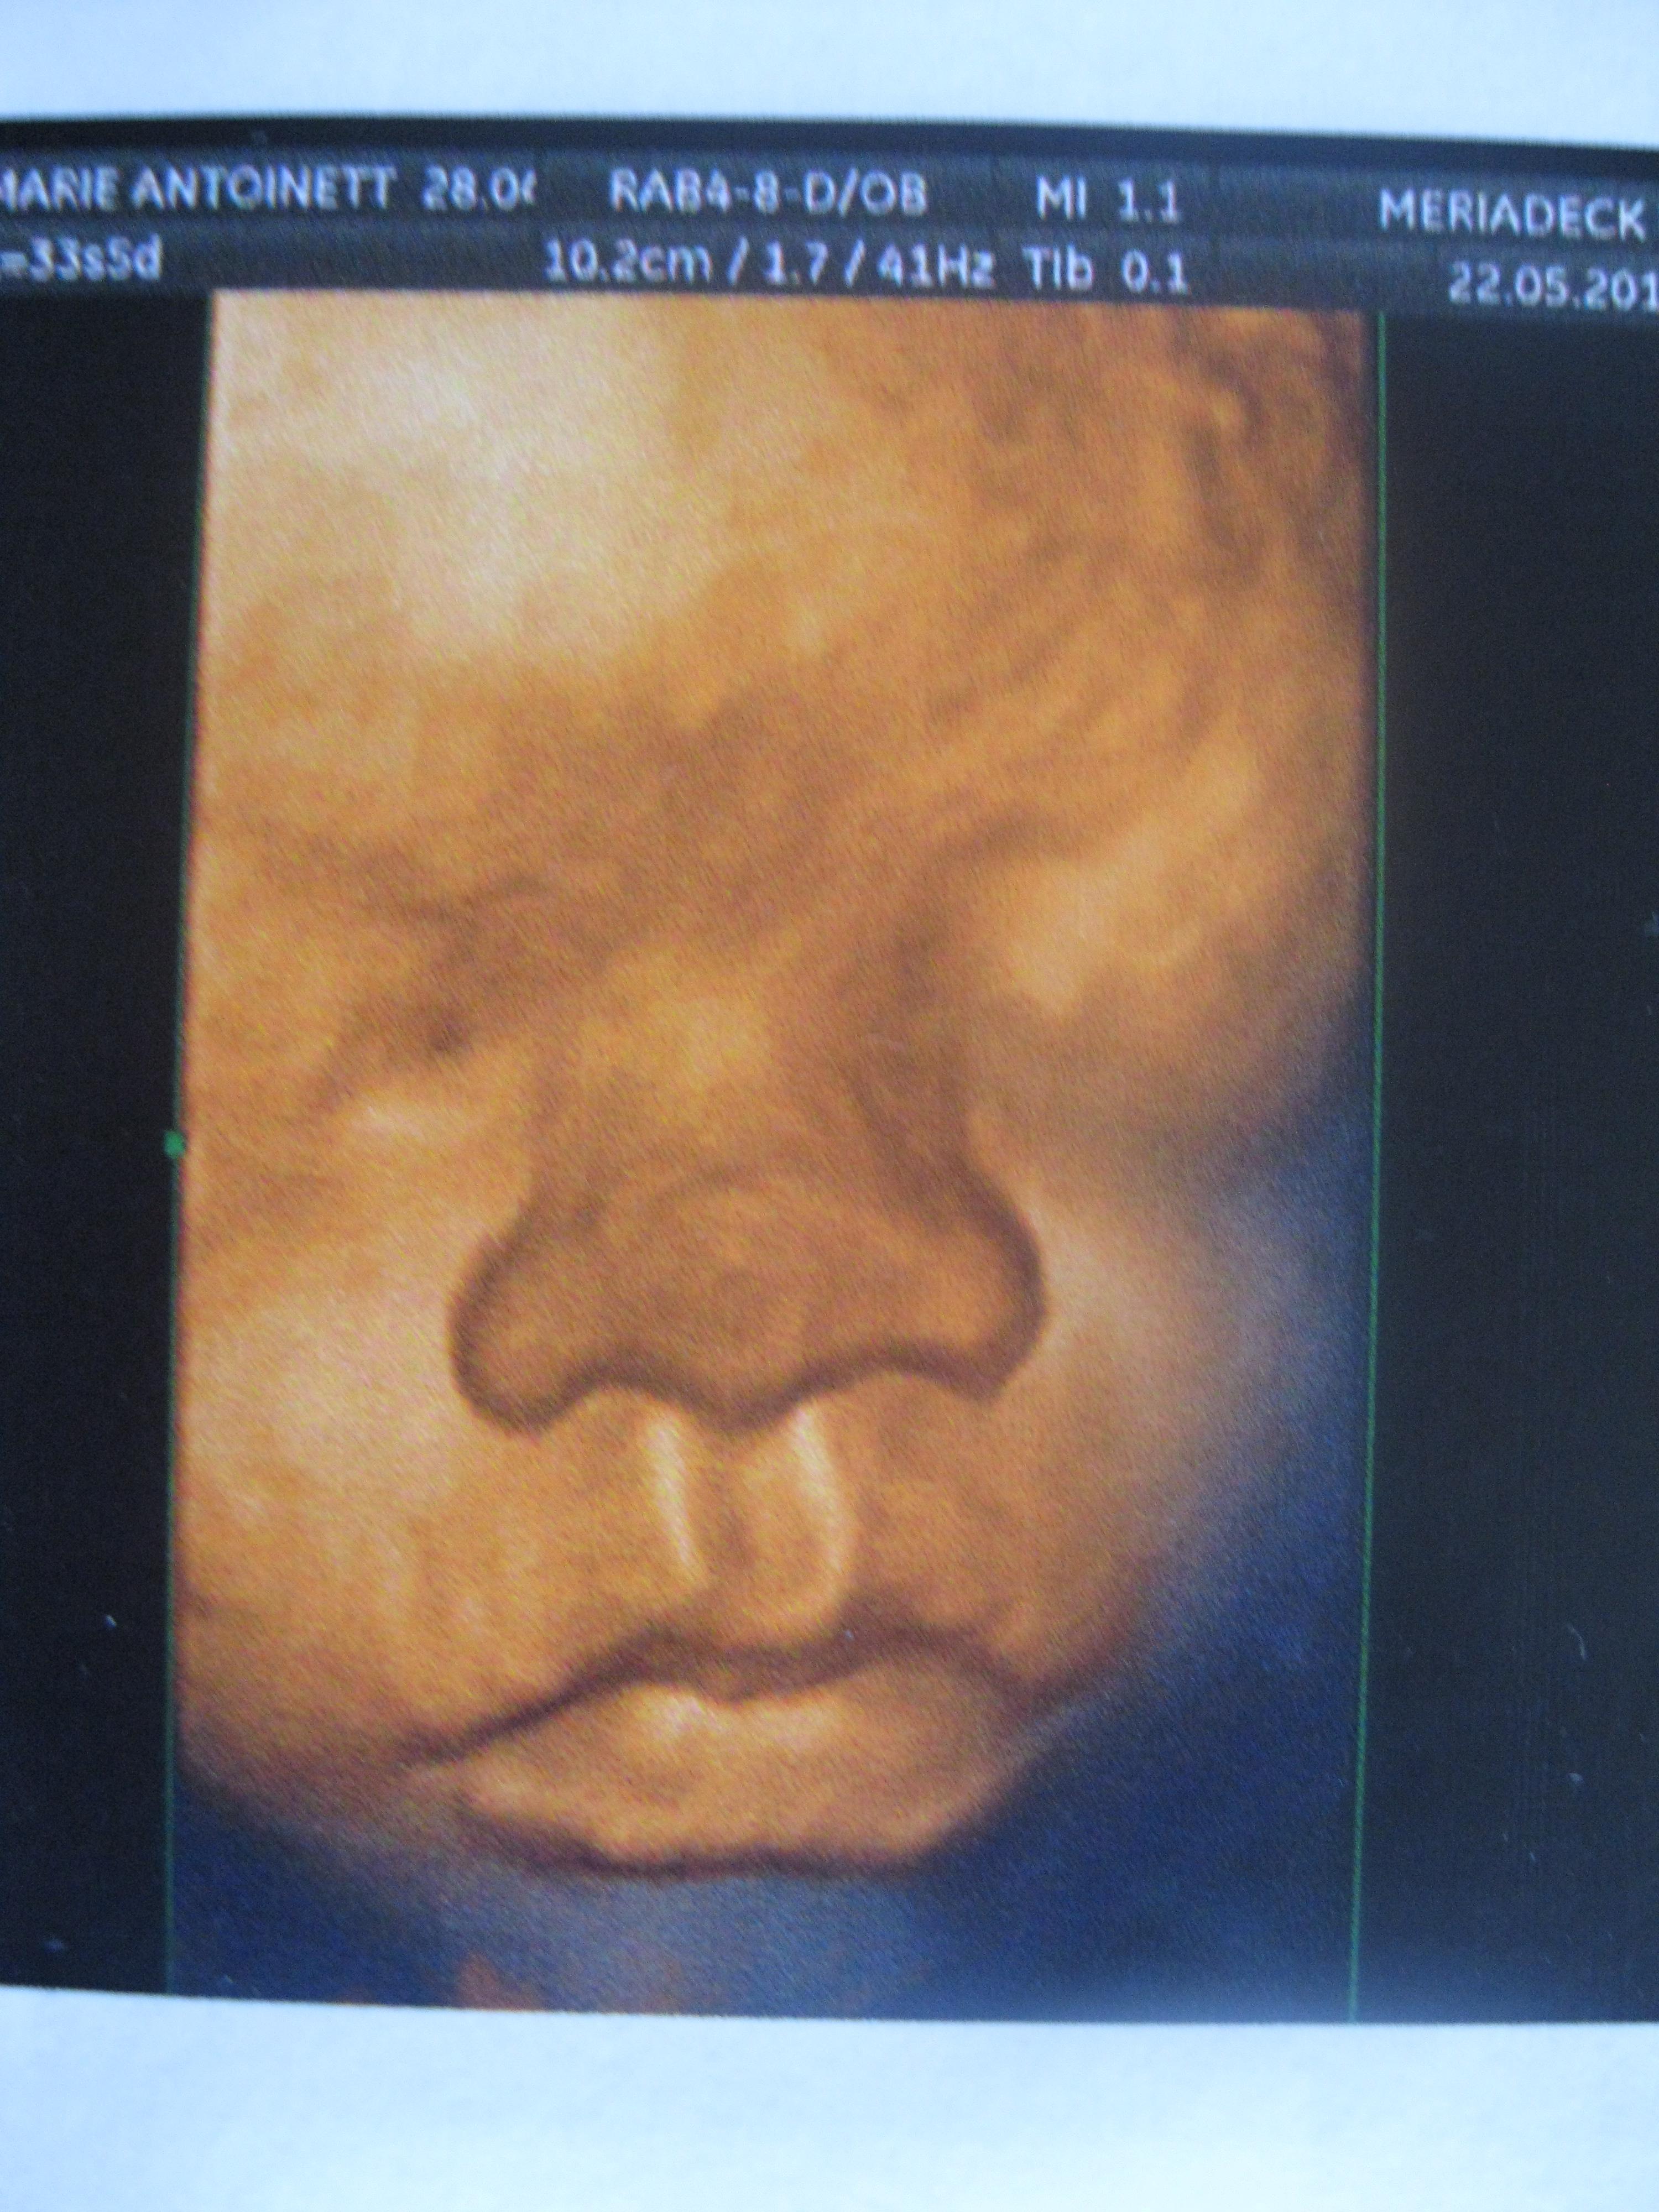

voyages des sens attend une réponse FAFCEA !!!! 28 Mai 2012 #1 Voilà la derniére echos de notre princesse

voyages des sens attend une réponse FAFCEA !!!! 28 Mai 2012 #4 oui !!!!!!!!! en plus elle a le nez de papa MDR

Doubi29 Inès, mon étoile qui brille depuis le 15juin 2012 31 Mai 2012 #8 zalmare a dit: Afficher la pièce jointe 501388 Cliquez pour agrandir... Trop chou!!!!!!!!